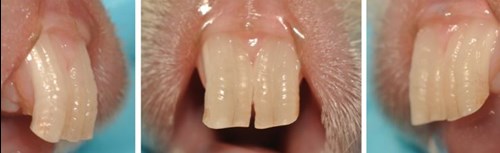

De hoeveelheid calcium (Ca) in het voer is daarvoor niet de enige factor die belangrijk is. Ook fosfor (P) en vitamine D (met name D3) spelen een rol. De opname van calcium in botten en tanden hangt namelijk samen met de hoeveelheid fosfor en vitamine D in het voer. De verhouding calcium:fosfor moet liggen tussen 1,5:1 en 2:1. Als deze verhouding verkeerd is, bijvoorbeeld als er meer fosfor dan calcium in het voer zit, of als er te weinig vitamine D is, kan botontkalking ontstaan en daardoor ook gebitsproblemen. Deze beginnen vaak met het doorgroeien van de kieswortels in het kaakbot. Een teken van een verkeerde calcium/fosforbalans zijn dwarse ribbels op de snijtanden of verkleuringen.

Ribbels op de tanden.

- tanden met dwarsribbels of verkleuring